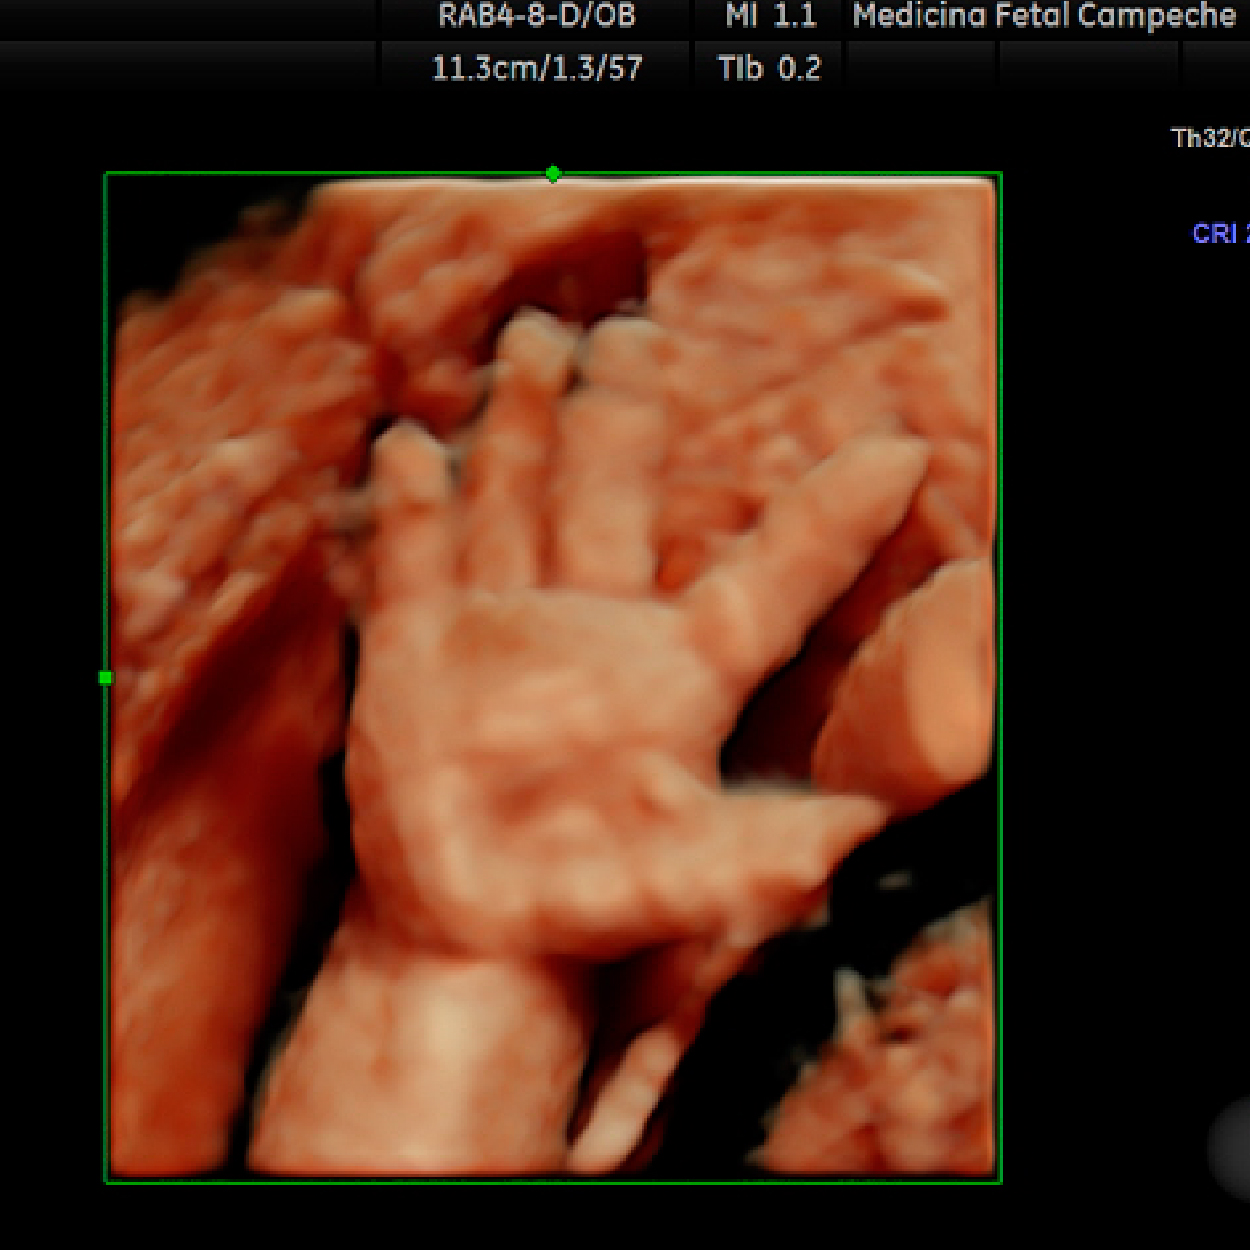

El ultrasonido es una técnica de diagnóstico por imagen; generada por de ondas de sonido que viajan a través de tu pancita, estas ondas de sonido son inofensivas para tu bebé, y nos permiten "fotografiar" y medir varias estructuras en formación.

8. Evaluación anatómica del feto después de las 11 semanas (preferentemente 12-14 semanas).